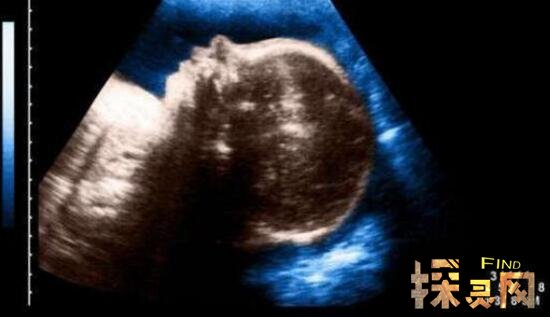

只有这个独眼婴儿出现在埃及东部的一家私人医院。当时负责接生的护士和医生都没想到,刚刚出现的婴儿就像一个怪物,只有一只眼睛,一张嘴巴,没有鼻子。所以医生推测独眼宝宝活不了几天了。

果不其然,每隔一段时间,大约五个小时后,新生的独眼婴儿悄然离世,但这个畸形婴儿却让人联想到希腊神话中只有一只眼睛的巨人。根据医生的说法,婴儿可能在子宫内受到了辐射的影响。

虽然这种畸形的发生并不少见,但86%的病例可以在怀孕期间通过超声检查进行调查。有报道称,南京的唐女士长期受到新车甲醛超标的影响。怀孕第三个月做超声波检查时,竟然查出胎儿有畸形,不得不引产。结果她真的是用一只眼睛引产了死婴。